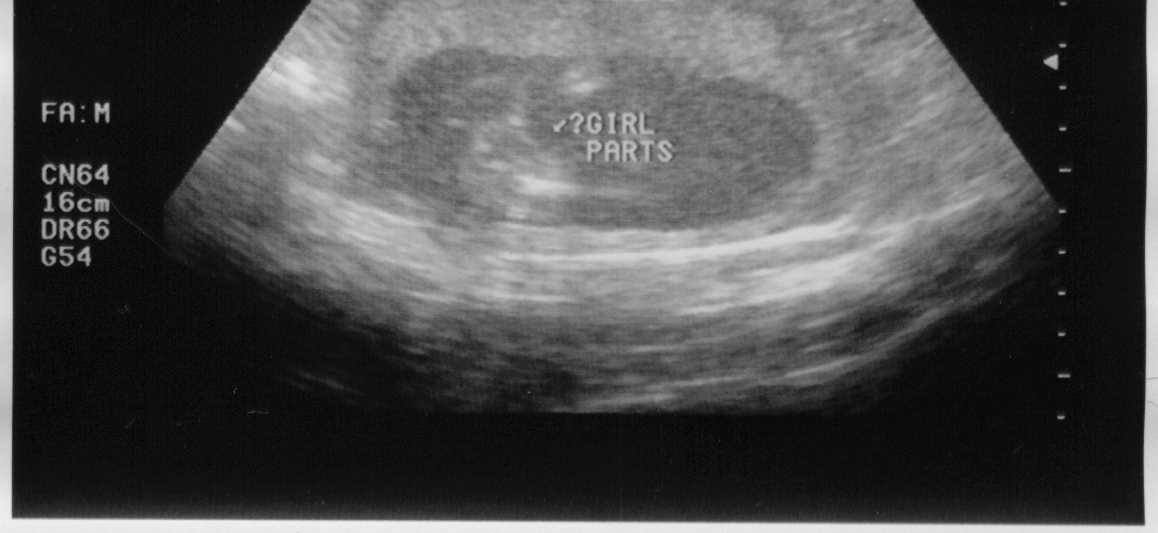

04-22-02 - Looks like I'm a GIRL!